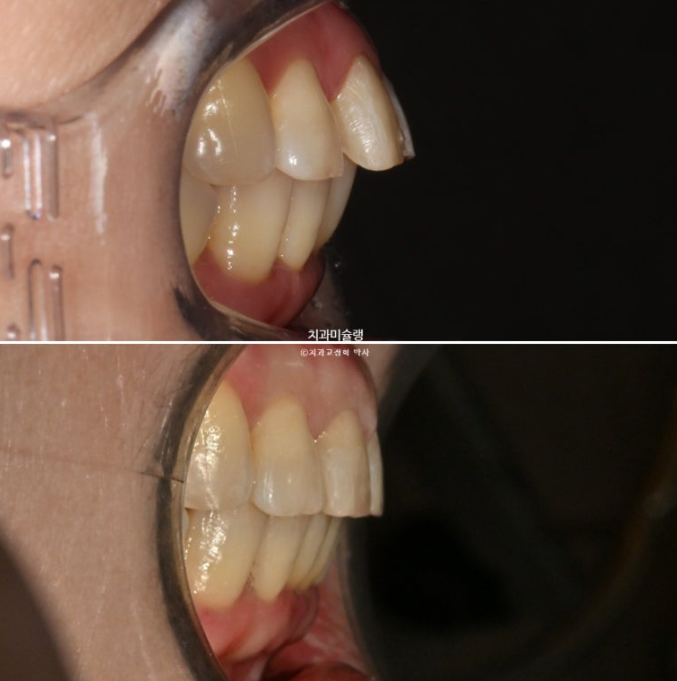

첫세트 장치 14개를 다 낀 후 모습입니다.

25년 1월 장치를 낀지 4개월 후 모습입니다.

25.01

앞니 사이 틈은 상당히 줄었고

이제 전후 비교해보겠습니다.

24.07~26.01

앞니 각도의 개선이 눈에 띕니다.

아래 앞니는 치간삭제와 함입으로 위 앞니 사이사이 벌어진 공간을 이용하여 뻗친 각도와 골출을 개선하였으며

위 아래 앞니 각각 1.5-2mm 가량 뒤로 들어갔습니다.